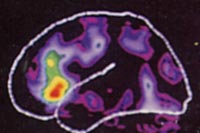

Netze und dynamische Systeme